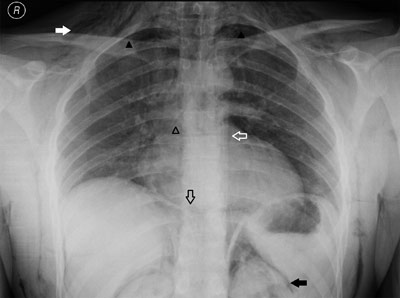

Figure A

Anteroposterior (AP) chest radiograph demonstrating diffuse subcutaneous emphysema (solid white arrow), a small pneumothorax in both apical lung fields (solid black arrowheads) and air outlining the thoracic aorta (hollow white arrow), the bronchial branches (hollow black arrowhead), both sides of the diaphragm (hollow black arrow) and both kidneys (solid black arrow).